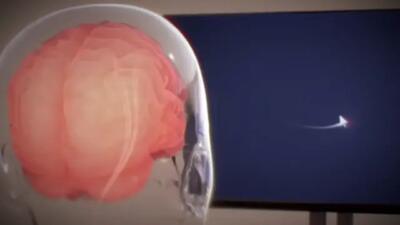

تراشه «نورالینک» در مغز نفر سوم ایمپلنت شد

ایلان ماسک اعلام کرد سومین فرد رابط مغز و رایانه نورالینک را دریافت کرده است.

سومین تراشه نورالینک در مغز یک بیمار کاشته شد

سومین ایمپلنت مغزی نورالینک در مغز یک بیمار کاشته شد.

کاشت ایمپلنت مغزی نورالینک در سومین بیمار

ایلان ماسک، اعلام کرد که ایمپلنت مغزی Neuralink به سومین بیمار پیوند زده شد و قصد دارد در سال ۲۰۲۵ حدود ۲۰ تا ۳۰ پیوند دیگر نیز انجام دهد.